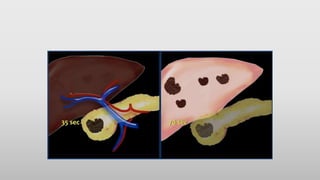

Triphasic cycle

HEART

DYE INTRAVENOUSLY

PORTAL VEIN 80%

PERFUSION LATE 50-60SEC

HEPATIC ARTERY 20%

PERFUSION EARLY 20SEC

LIVER PARENCHYMAL INTERSTITIAL

TISSUE

Triphasic cycle HEART DYE INTRAVENOUSLY PORTALVEIN 80% PERFUSION LATE 50-60SEC HEPATIC ARTERY 20% PERFUSION EARLY 20SEC LIVER PARENCHYMAL INTERSTITIAL TISSUE